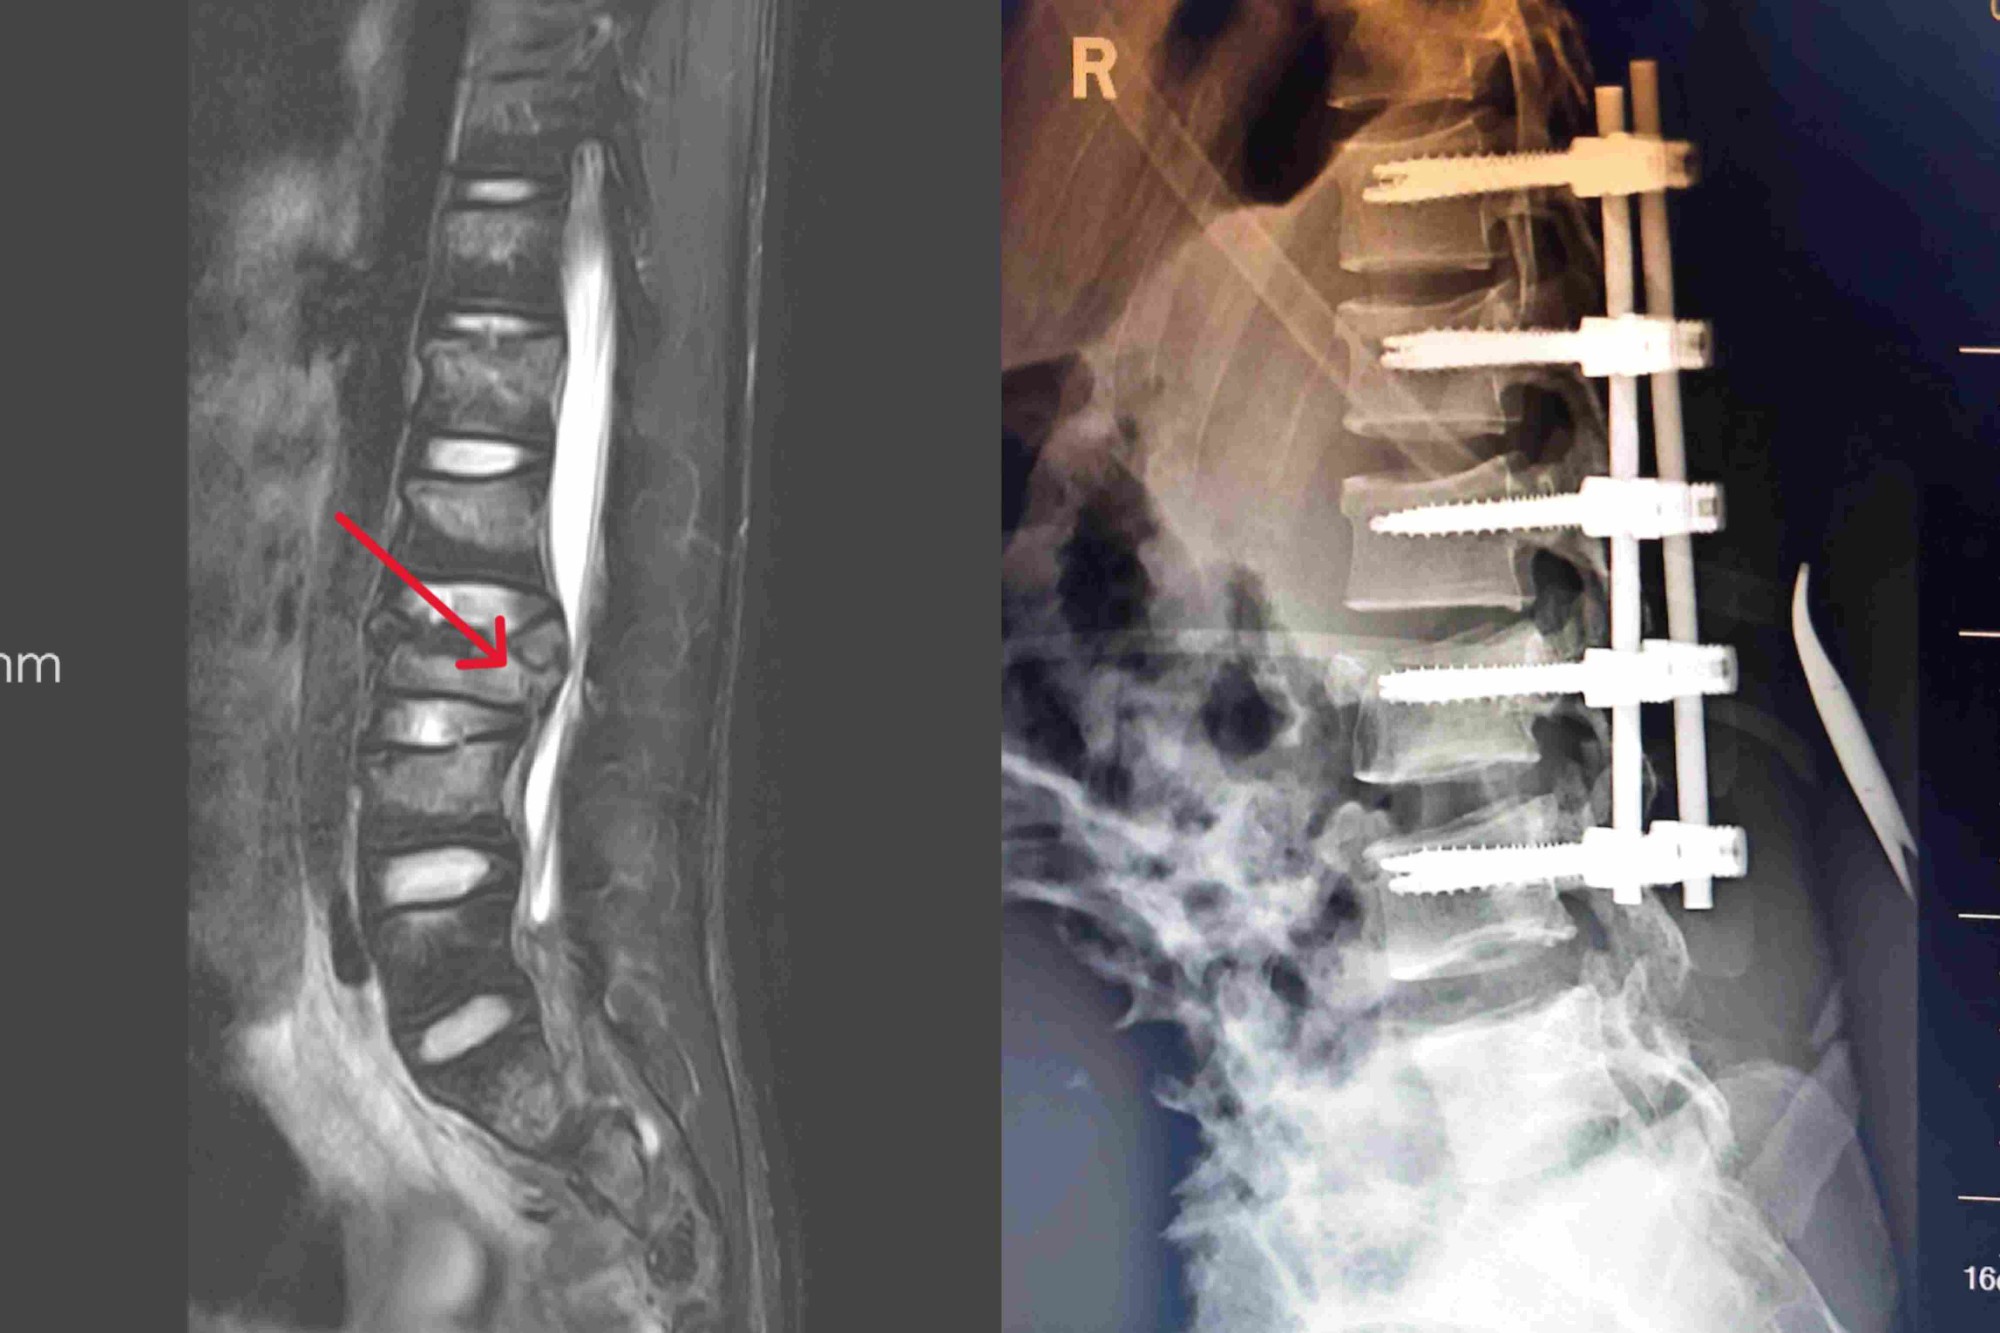

患者因高处坠落导致右足先着地,巨大冲击力造成全身多发伤,被紧急送入院。入院时已呈意识模糊、血压骤降、呼吸急促等危重状态。急诊CT明确诊断为右踝关节粉碎性骨折、骨盆骨折、气胸以及腰1、腰3椎体压缩性骨折,凝血功能提示早期DIC伴失血性休克,生命指标濒临危急值。医院立即启动危重患者救治预案,神经外科、脊柱外科、胸外科、输血科等多学科专家迅速集结会诊,为患者制定了周密的个体化救治方案。

经过数日积极救治,患者休克得以纠正,DIC指标恢复正常,气胸改善,生命体征趋于稳定,已成功度过危险期。病情稳定后,神经外科唐乐剑主任医师团队经全面评估与讨论,为这位年轻患者实施了T12~L4椎弓根固定术联合椎管内骨折碎片取出术。手术顺利完成,有效修复了腰椎结构,为患者日后功能康复奠定了坚实基础。